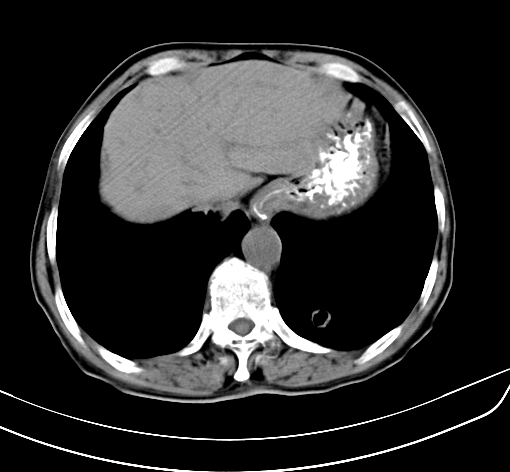

病人 男 70 咳嗽 胃部不适 2月余

胆囊壁增厚,与临近肝实质边界不清,临近肝实质内可见大片边界不清之低密度区,肝门区密度亦有减低,部分结构不清,尾叶前方可见块状影,肝右叶可见多枚边界不清之圆形低密度区,肝内胆管扩张征象,结合病史考虑1胆囊癌肝内转移,肝门区淋巴结转移,门脉癌栓待排2肝内胆管扩张3建议增强扫描

肝脏多发大小不等低密度灶,边界不清,肝门区结构不清,肝内胆管轻度扩张,胆囊密度不均匀,内见软组织样密度影,与相临肝脏边界不清.考虑:1、胆囊ca侵犯肝脏并肝内多发转移,肺上也有结节影,转移?建议强化扫描.2、胃充盈不好,如怀疑有病变最好建议做相关检查.

胆囊壁增厚,周围模糊不清,肝内多发低密度影,胃充盈欠佳,胃壁增厚,外形尚规整,考虑胆囊炎、胆囊癌肝内转移?建议胃肠道进一步检查或增强扫描。